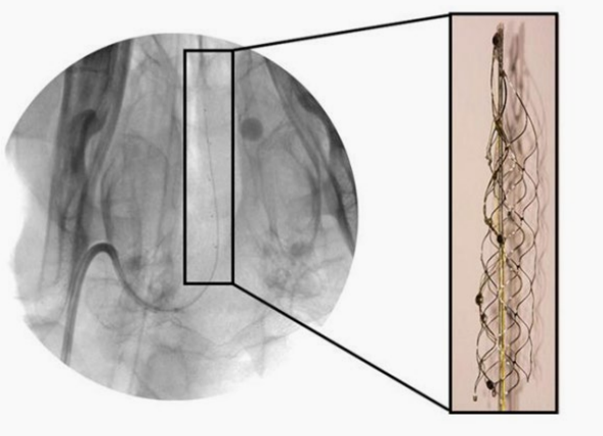

然而,在电极材料的选择中,镍钛合金并不是首选的选择。Wong等研究了镍钛诺、铂(铂)和不锈钢(SS)作为电极材料的性能。如图2所示,结果显示Pt和SS的电导率明显优于NiTi。由于Pt与生物细胞具有优越的生物相容性,比SS得到更广泛的应用。因此,采用了Pt电极与NiTi支架的组合。

图2 (a)三种不同材料的阻抗大小和频率之间的关系

(b)三种不同材料的相位角与频率之间的关系